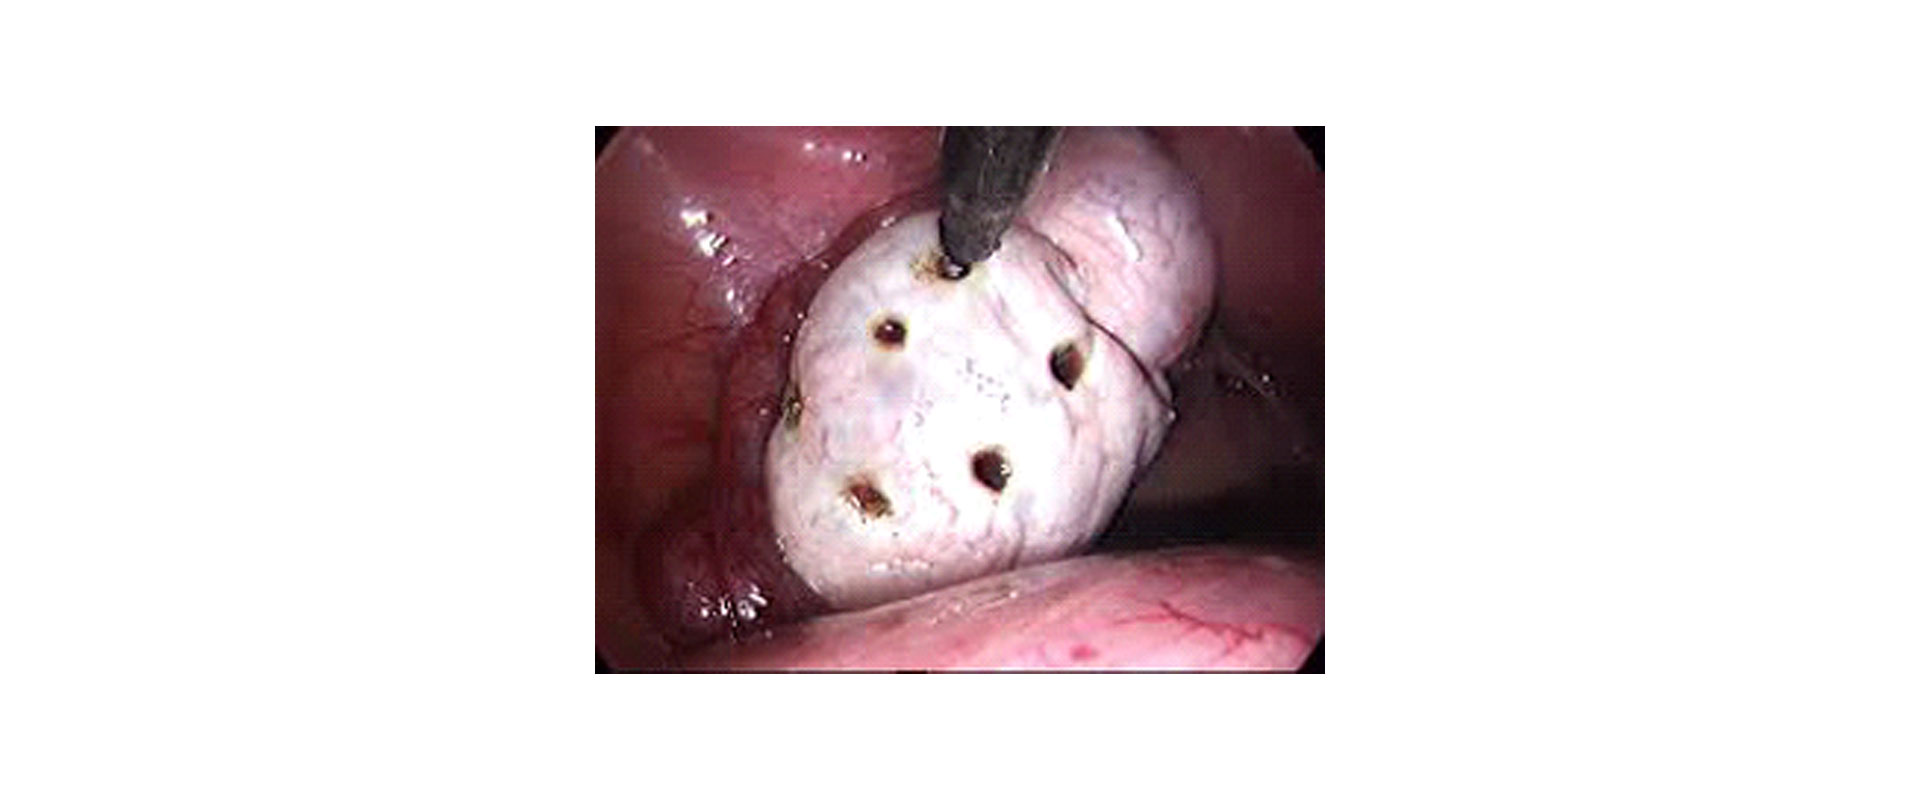

⦁ ΧΕΙΡΟΥΡΓΙΚΗ ΕΠΕΜΒΑΣΗ

Η λαπαροσκοπική επέμβαση δημιουργίας οπών με διαθερμία ή Laser στις ωοθήκες (Laparoscopic ovarian drilling) είναι μια επεμβατική μέθοδος που εφαρμόζεται είτε σε αποτυχία των γοναδοτροπινών, είτε σαν εναλλακτικός τρόπος πρόκλησης ωορρηξίας ενός ωαρίου, αποφεύγοντας έτσι την πιθανότητα πολύδυμης κύησης.